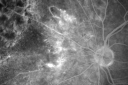

67-year-old woman has a macular pucker in the left eye. She had radiation for a melanoma in that eye in 2006. She had cataract surgery February of 2009 and a posterior sub-Tenon Kenalog injection in April. Her vision in the left eye is hazy and she has trouble seeing out of it. VISUAL ACUITY: OS 20/70. IOP: 11. The posterior chamber intraocular lens is in good position. EXTENDED OPHTHALMOSCOPY: OS: Vertical C/D ratio is 0.3. There are 2+ vitreous cells. There is a 3+ epiretinal membrane. There is radiation and retinopathy nasal to the optic nerve and there is a melanoma, which has regressed superonasally. OCT SCAN: The OCT scan shows an average central foveal thickness of 347 microns, which is stable. Photos confirm clinical findings. FLUORESCEIN ANGIOGRAPHY: Fluorescein angiography shows some irregularities where the macular pucker is and the radiation retinopathy is nasally away from the optic nerve with the capillary closure over the tumor. IMPRESSION: 1. STATUS POST RADIATION FOR MELANOMA – LEFT EYE 2. MACULAR PUCKER – LEFT EYE DISCUSSION: I explained to the patient with 20/70 vision with the macular pucker, she is a reasonable candidate for macular pucker surgery. She would like to try that if it would improve her vision. I told her there is an 80 percent chance of her vision improving about half way to normal with the therapy. (Vision improved to 20/40 6 months after vitrectomy for pucker)

Radiation Retinopathy and Macular Pucker 4 years following Brachytherapy (Plaque) for Nasal Melanoma699 views67-year-old woman has a macular pucker in the left eye. She had radiation for a melanoma in that eye 4 years aog. She had cataract surgery 2 years ago and a posterior sub-Tenon Kenalog injection in 7 months ago. Her vision in the left eye is hazy and she has trouble seeing out of it. VA OS 20/70. 00000